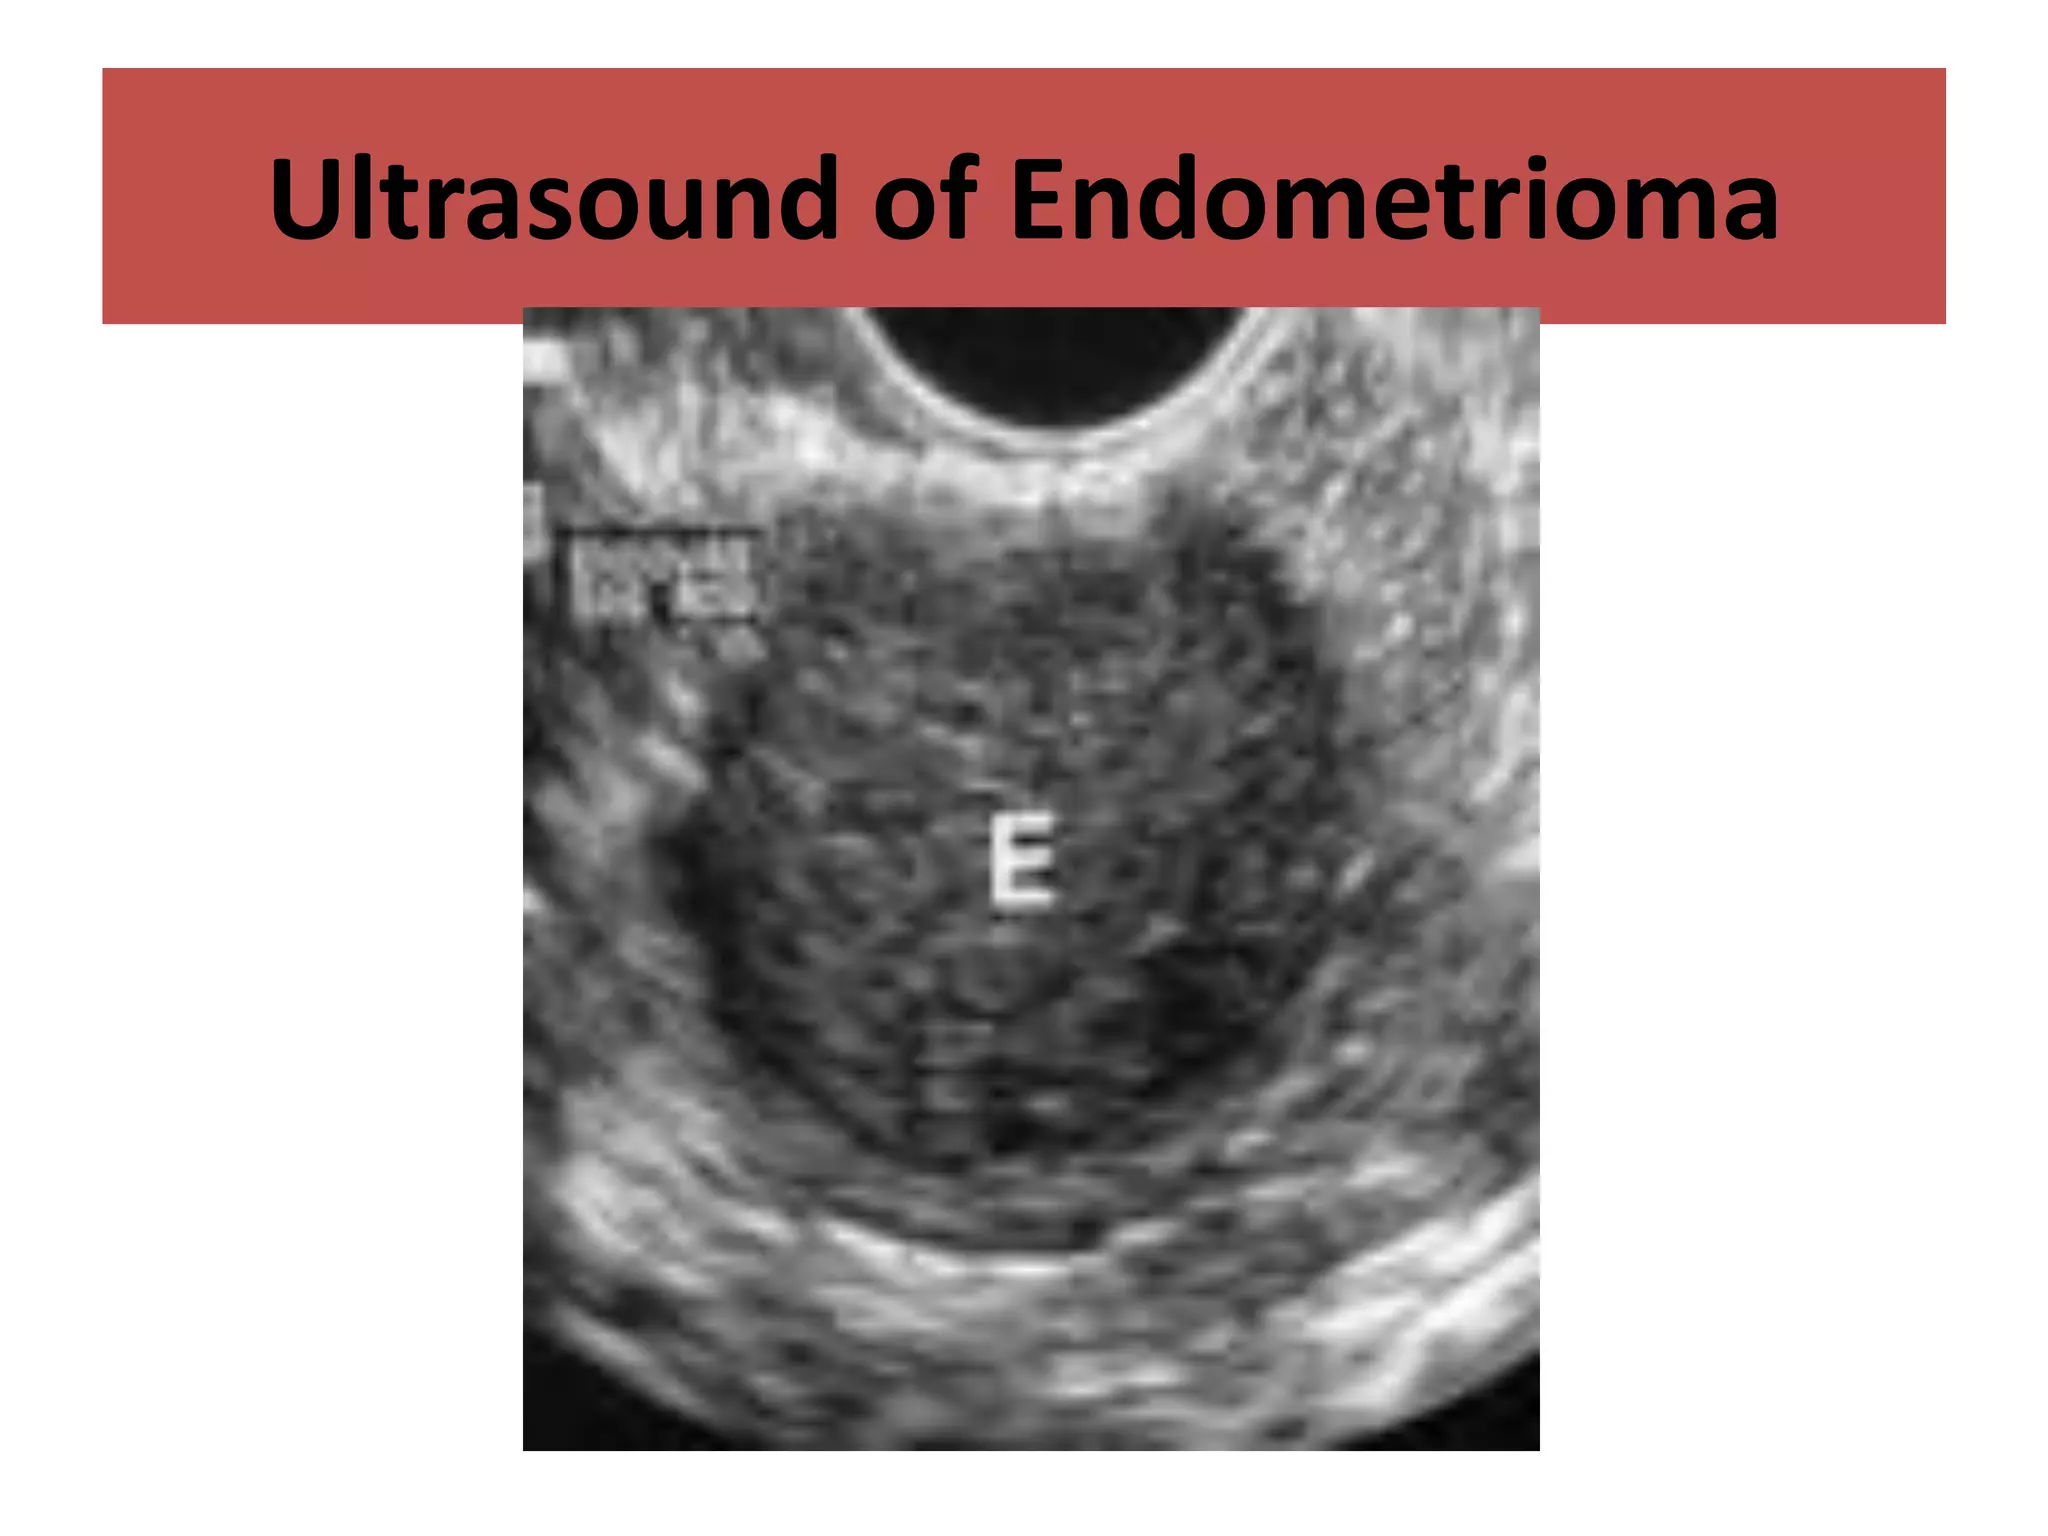

Transvaginal Ultrasound:

• Low level internal echoes

• Thick walled

• Homogeneous “ground glass” appearance

• Unilocular or Multilocular

• Often solid appearing or cystic

• Can show varying degrees echogenicity (even

anechoic) in locules with fluid levels

• Can show punctate echogenic foci (wall or central

calcification) with distal shadowing

• Round Shape

Regular Margins

Ultrasound of Endometrioma